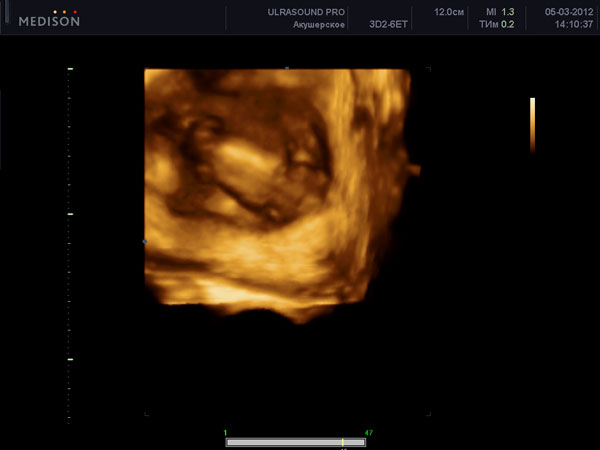

Допологова (антенатальна) передача герпетичної інфекції плоду виникає в 5% випадків від матерів з первинною формою генітального герпесу. При первинній формі генітального герпесу існує період, коли вірус герпесу з'являється у великих кількостях в крові вагітної і таким чином передається через плаценту плоду.Етот механізм внутрішньоутробного інфікування характерний і для інших TORCH-інфекцій (TORCH (toxoplasmosis, other infections, rubella, cytomegalovirus, and herpes simplex). При цьому у плода можуть виникати такі вади розвитку як мікроцефалія, мікроофтальмія, внутрішньочерепні кальцифікати і хореоретініт.